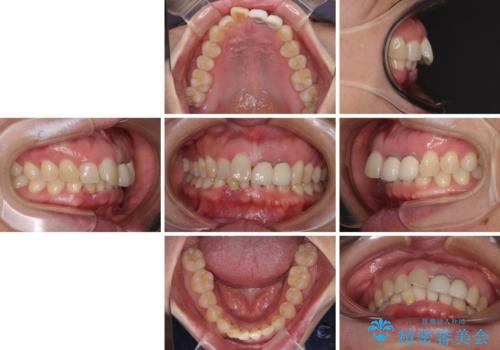

前歯のインプラント治療 折角なので矯正治療できれいな歯並びに

- 下顎前歯が抜けそうとのことで来院された患者様です。

初診の状態ではすぐにでも抜けそうな状態で、インプラントによる補綴治療を行うこととしました。

インプラント治療に際し、前歯の叢生に対する矯正治療を提案したところ、興味を持たれたので、インビザライン・ライトによる矯正治療を行うこととしました。

抜歯後にスペースができると恥ずかしいため、抜歯した歯を接着剤で固定した上で矯正治療を行い、その後インプラントやオールセラミッククラウンの装着を行うこととしました。